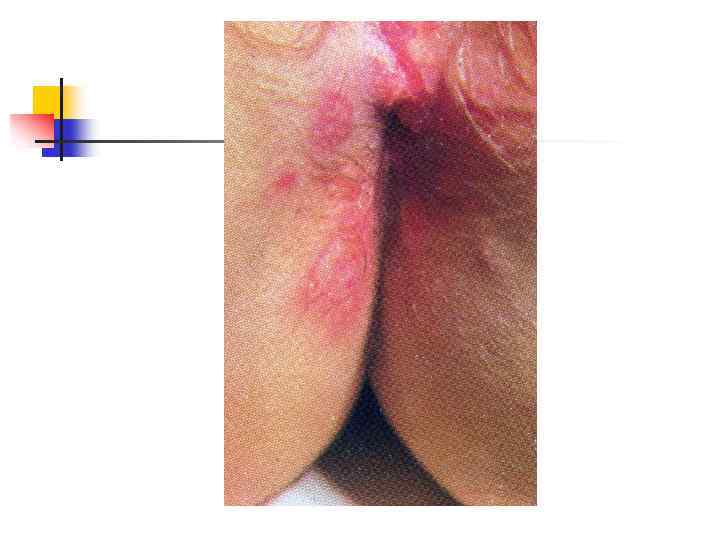

Герпес половых органов: герпетический проктит У этого больного – СПИД. Герпесом поражены прямая кишка, заднепроходный канал и кожа промежности. Видны многочисленные глубокие язвы с чёткими границами и гнойным отделяемым. Боли при дефекации; язвы чрезвычайно болезненны.

Герпес половых органов: герпетический проктит У этого больного – СПИД. Герпесом поражены прямая кишка, заднепроходный канал и кожа промежности. Видны многочисленные глубокие язвы с чёткими границами и гнойным отделяемым. Боли при дефекации; язвы чрезвычайно болезненны.